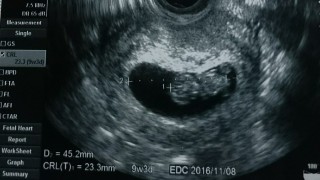

8w6dかと思っていたけど9w3dで予定日算出されました。4日ワープしました。GS45.2mmCRLは23mm。2w前はGS20.7mmCRL8.3mmでした。GSは倍に、CRLは3倍弱に成長していました。

9w3d、2センチくらいで順調だそうです! 心臓とあんよがぴょこぴょこ動いてて可愛かったー!

手をバタバタさせながら体をうねうねしてました。 経膣エコーでしたが夫にも見てもらいました。 夫も動いてるところが見れたのがよかったとのことです。 つわりがないので逆に心配ですが、元気に動いていたので安心しました。 23.6mmで、出産予定日変更なしです。

計算では8w6dでしたが大きさで9w3dになり予定日が4日早まりました。 大きさは23.8mmでエコーの最中にお尻をぷりぷり動かしてました(^^) 母子手帳も貰って徐々に実感が沸いてきました。まだつわりがしんどいですが頑張ります。前回の妊娠は侵入奇胎で残念な結果になってしまったので今回は順調に育って欲しいです。